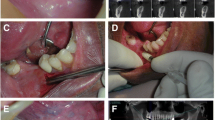

All 25 patients received immediate or delayed implant surgery with bone graft using a small buccal incision and subperiosteal tunneling technique. Under local anesthesia using 1 % lidocaine with 1:100,000 epinephrine, a small vertical and/or horizontal incision of less than 10 mm was made in the mucoperiosteum of the labial or buccal sides. A subperiosteal cavity was prepared with a periosteal elevator, and a selection of bone graft materials was placed into the tunnel to augment the deficient alveolar ridge. Various bone graft materials such as autogenous demineralized dentin matrix (ADDM), allograft, and xenograft were selected based upon patients need determined by an experienced oral surgeon. The incision was then closed with 4–0 Vicryl (polyglactin; Ethicon Inc., Sommerville, NJ) using a simple interrupted suture technique. After suture, the graft bone site was molded with a finger to shape appropriate forms (Fig. 1). Patients who underwent surgery took antibiotics (amoxicillin/clavulanate; Augmentin®, Ilsung Pharmaceuticals Co., Seoul, Korea) and a non-steroidal anti-inflammatory drug (talniflumate; Somalgen®, Kunwha Pharmaceutical Co., Seoul, Korea) for 5 days postoperatively. Extra-oral pressure dressing was applied for 3 days to minimize postoperative swelling and 100 mL of 0.1 % chlorhexidine mouth gargling (Hexamedine®, Bukwang Pharm, Ansan, Korea) was prescribed for oral hygiene maintenance. Sutures were stitched out between 10 and 14 days after the surgery and patients were routinely followed every 3 months for clinical and radiological evaluation of implant status.

Intraoral photographs of minimal invasive horizontal ridge augmentation using a subperiosteal tunneling technique. a Deficient alveolar ridge. b Small vertical incision in the buccal side. c Preparation of subperiosteal cavity. d Bone graft material insertion into the tunnel. e After the placement of bone graft material. f Closure of the tunnel